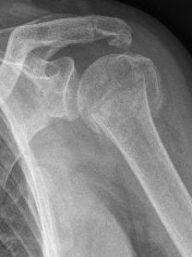

Picture: The subcapital humeral fracture shown here in the axis is not broken and only slightly bruised, so that a conservative therapy is possible. The left image shows the follow-up after 3 weeks. The patient has already started physiotherapy. The x-ray shows an increase bone healing.